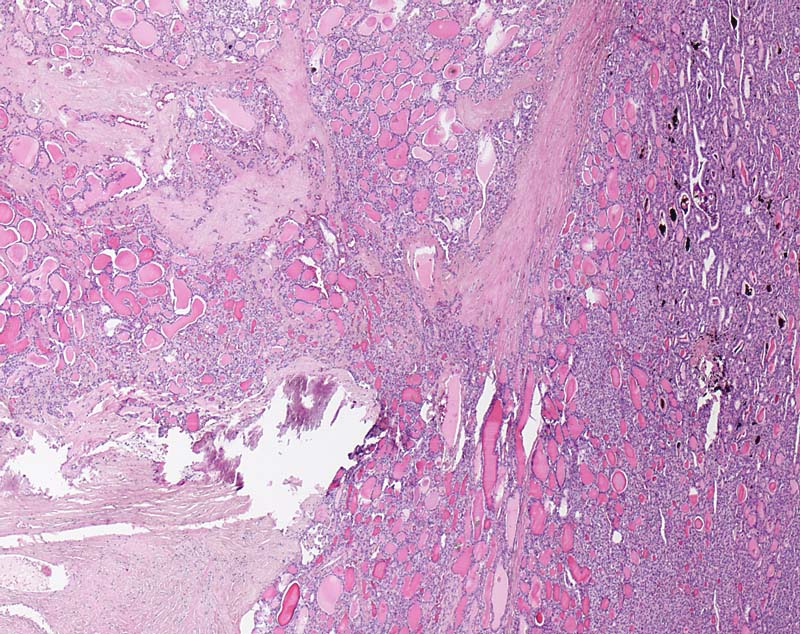

Grob invasives follikuläres Schilddrüsenkarzinom

Der follikuläre Tumor durchbricht die dicke bindegewebige Kapsel und infiltriert breitflächig das angrenzende Gewebe (links im Bild).

Kapseldurchbrüche mit ausgedehnter Invasion des benachbarten Gewebes fanden sich an zahlreichen Stellen. Somit handelt es sich um ein grob invasives follikuläres Karzinom.

Follikuläre Neoplasie der Schilddrüse